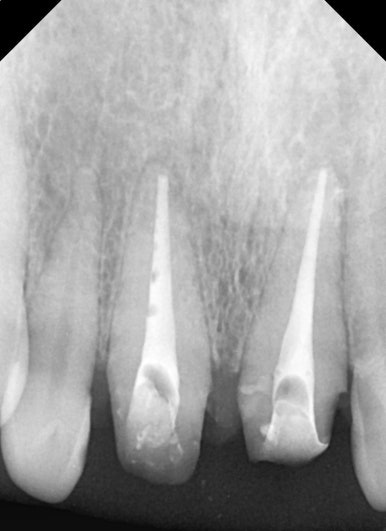

엑스레이 검사 결과, 뿌리 끝에는 염증도 생겨 있었습니다.

단순히 겉모습의 문제만이 아니라, 치아 뿌리 쪽도 치료가 필요했던 상황이었습니다.